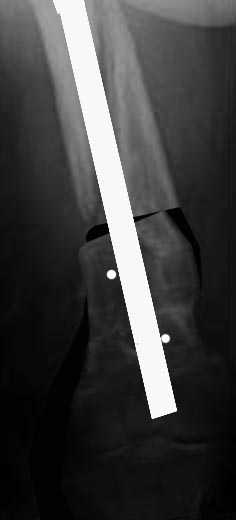

Антеградный канал уже есть, зачем делать еще и ретроградный. Канал рассверлить и взять гвоздь уже серьезного диаметра, от 12 мм. Но здесь одна серьезная проблема - вальгус. Наверно (надо скиаграмму сделать и уточнить) просто изменением оси его не устранить, потому что промежуточный отломок по медиальной стороне сросся с периферическим под углом, он не даст правильно расположить мыщелки бедра к диафизу.

Для восстановления оси достаточно поперечной остеотомии дистального отломка по нижнему краю центрального. В периферическом отломке ввести

спереди назад отклоняющие спицы или винты, чтобы гвоздь пошел не по старому каналу, а куда надо. Приблизительная схемка в приложении.

Гвоздь надо запереть в дистальном отломке более чем 2 винтами. Лучше, чтобы и винты были потолще.